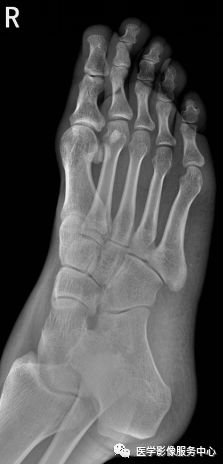

右足第5跖骨基底部见骨折线,断处稍分离移位。右足第5跖骨基底部骨折。

Warmreminder: 儿童时期足第5跖骨处有骨骺存在,骨骺线易与骨折线混淆,小妙招给你,骨骺线的长轴一般是与第5跖骨长轴平行,而第5跖骨多是横行骨折,换言之骨折线与第五跖骨长轴垂直。